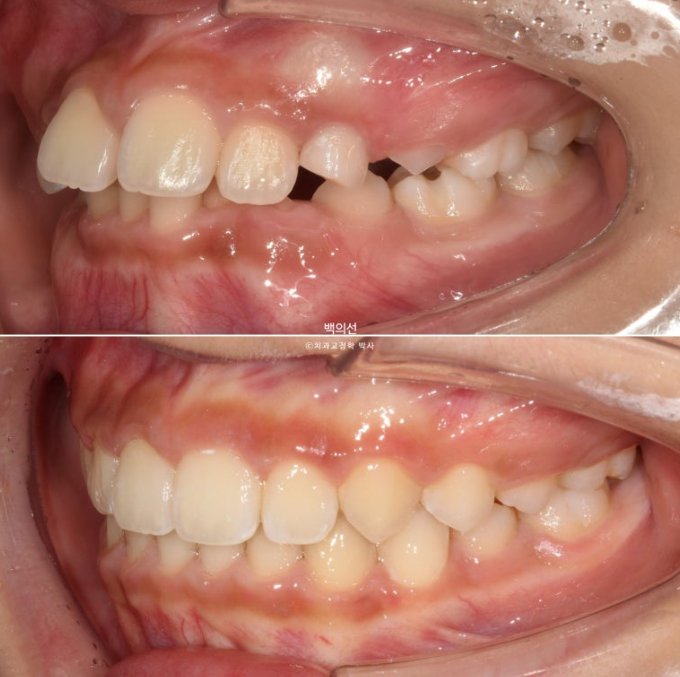

23.07~25.07

1차 세트 6개월 치료, 9개월간 휴식기, 7개월간 2차세트 치료를 거쳐 마무리된 모습입니다.

덧니와 과개교합의 개선입니다.

앞니 돌출의 개선

교합의 개선